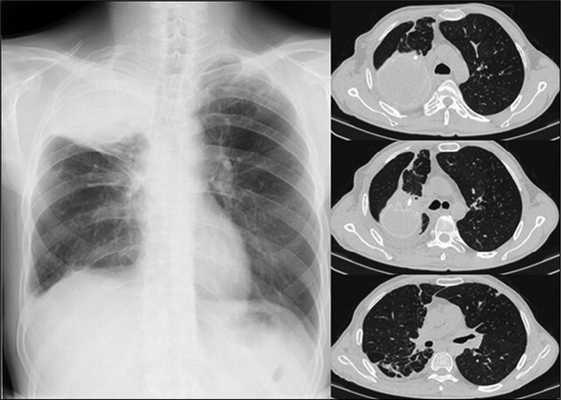

На обзорных рентгенограммах и компьютерной томографии легких определяется фиброзное сморщивание верхней доли и S6 правого легкого, S1-2 левого легкого. Множественные разнокалиберные тонко- и толстостенные каверны: крупные в верхних отделах и мелкие в нижних отделах правого легкого (рис. 1).

Рис. 1. Рентгенографическое (А) и КТ (Б) исследование органов грудной клетки у больного А. при поступлении (описание в тексте)

Функция внешнего дыхания: жизненная емкость легких 62,9% д.в., объем форсированного выдоха за 1 сек 48,1% д.в.; газовый состав крови: РаО2 61 мм рт.ст., SaО2 90,9%, РаСО2 42 мм рт.ст. Снижение вентиляционной способности легких по смешанному типу, умеренное снижение жизненной емкости легких. Умеренная артериальная гипоксемия.